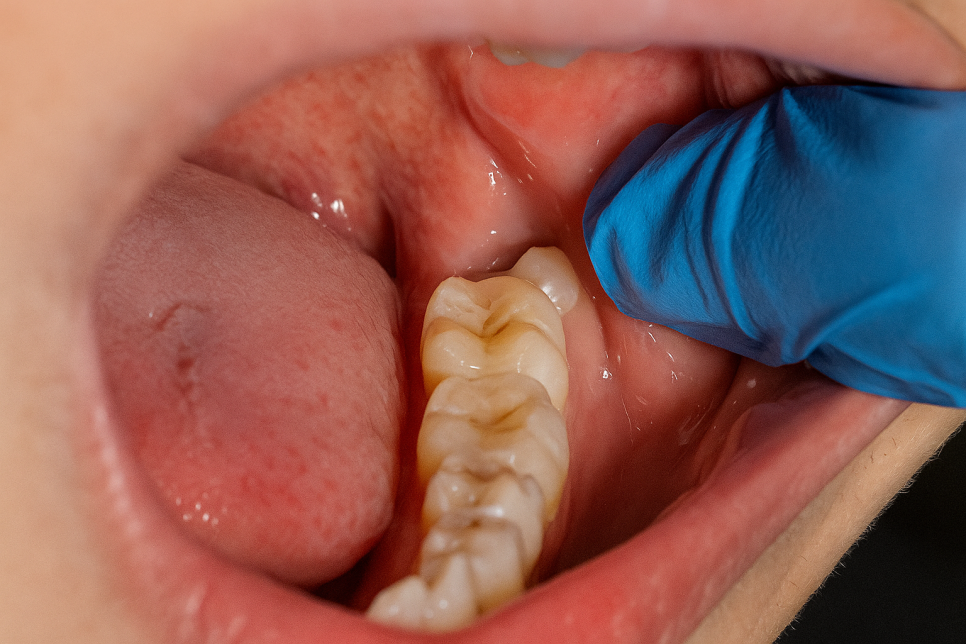

그 중에서도 잇몸 속 깊이 매복된 것은

그 고민의 깊이를 더욱 더하게 됩니다.

제3대구치는 어금니 옆,

구강 내 맨 안 쪽에 위치합니다.

그래서 양치하는 것도 어렵고,

충치가 생겨서 치통을 일으킬 수 있습니다.